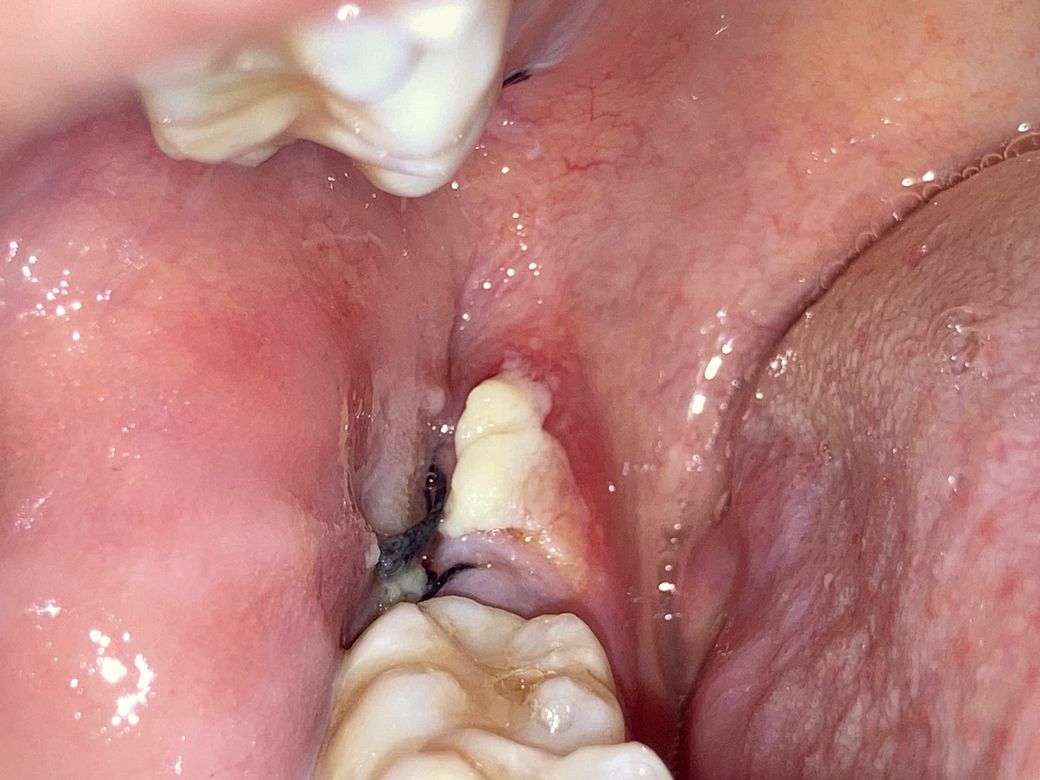

사랑니 발치 3일. 하얀덩어리의 정체?

이게 뭔지 알 수 있을까요 ㅜㅜ 위아래 동시에 뽑앗는데 아래에만 생겼어요 혹시 몰라서 제거 안했고 가글 열심히 했어요 약도 잘 챙겨먹구요 ㅜㅜ 다른 아빨 뺏을때는 이러지 않았어요

• 2번 째 사진

사랑니를 뽑는 과정에서 연조직에 자극이 되었다면 해당 부위가 하얗게 가피처럼 생성될 수 있습니다.

통증이 있거나 냄새가 나지 않는다면 큰 문제가 되지 않을 것으로 생각되지만 걱정이 된다면 치과에서 진료를 받아 보는 것이 좋습니다.

하얀색 막은 상피세포가 차오를 때 생기는 막입니다. 통증이 심하거나 악취가 나지 않으면 잘 나을겁니다.

지혈제가 아니라면 음식물같습니다. 일단은 치과에 가셔서 소독을 한번 받아보시는게 좋을것같습니다.